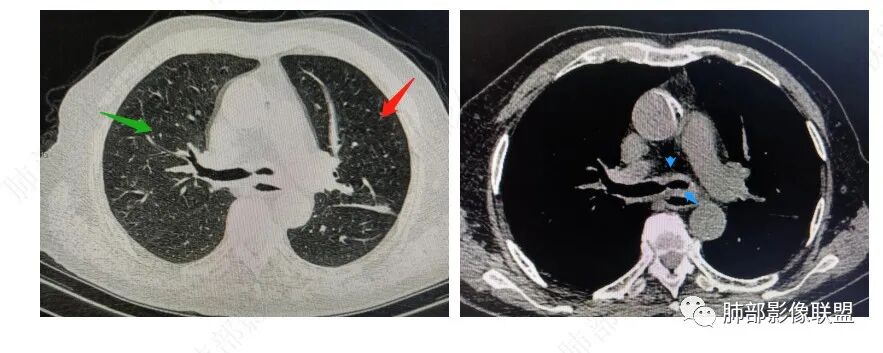

支气管弥漫性增厚、到闭塞、肺不张,肺部可见树芽征、小叶间隔增厚(类似癌淋)、叶间胸膜增厚、这些征象都指向支气管结核伴淀粉样变性。如果非要鉴别的话,考虑一下曲霉菌、鳞癌

前后5个月左主支气管壁进行对称增厚及塌陷狭窄(解释咳喘加重),左侧胸廊变窄,左肺叶体积缩小,有实质和间质混合病变,向外周间质引流特点。复查右肺上尖后段多发小树丫及融合特点,TB?支气管镜活检。

左肺下叶支气管闭塞了

左侧支气管壁弥漫增厚,腔狭窄,但是未见明显肿块

弥漫支气管壁增厚鉴别:

1、结核

2、曲霉菌

3、淀粉

4、血管炎

5、软骨类

肿瘤弥漫的少